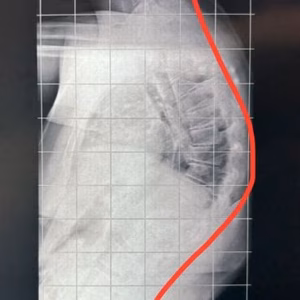

Conheça uma das causas de corcunda (cifose). É muito comum vermos pessoas com uma postura ruim.

Informações sobre escoliose do adolescente e a importância do diagnóstico precoce.